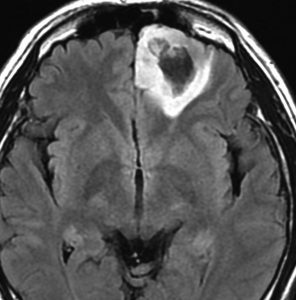

無症状で発見された若年成人の左前頭葉グリオーマです。ガドリニウム(右側)では全く増強されません。手術で全摘出しました。組織像は退形成性星細胞腫でした。壊死も血管内皮増生,多核巨細胞なし,核の腫大,形不整,多形成あり,免疫組織染色とシークエンスともにIDH野生型,1p/19q共欠失なし,MIB-1染色率 10%,nuclearATRX欠失。

この例を,グレード3とするかグレード4とするかの定義はありません。

膠芽腫グレード4に準じた治療を行いました。拡大局所50Gy/25fr, 局所10Gy/5frとテモゾロマイド併用の初期治療とテモゾロマイド維持療法2年間でした。

7年後のMRIには再発はありませんでした。

振り返って見れば,この例はIDH野生型だけど,きっと星細胞腫グレード3だったんでしょう。